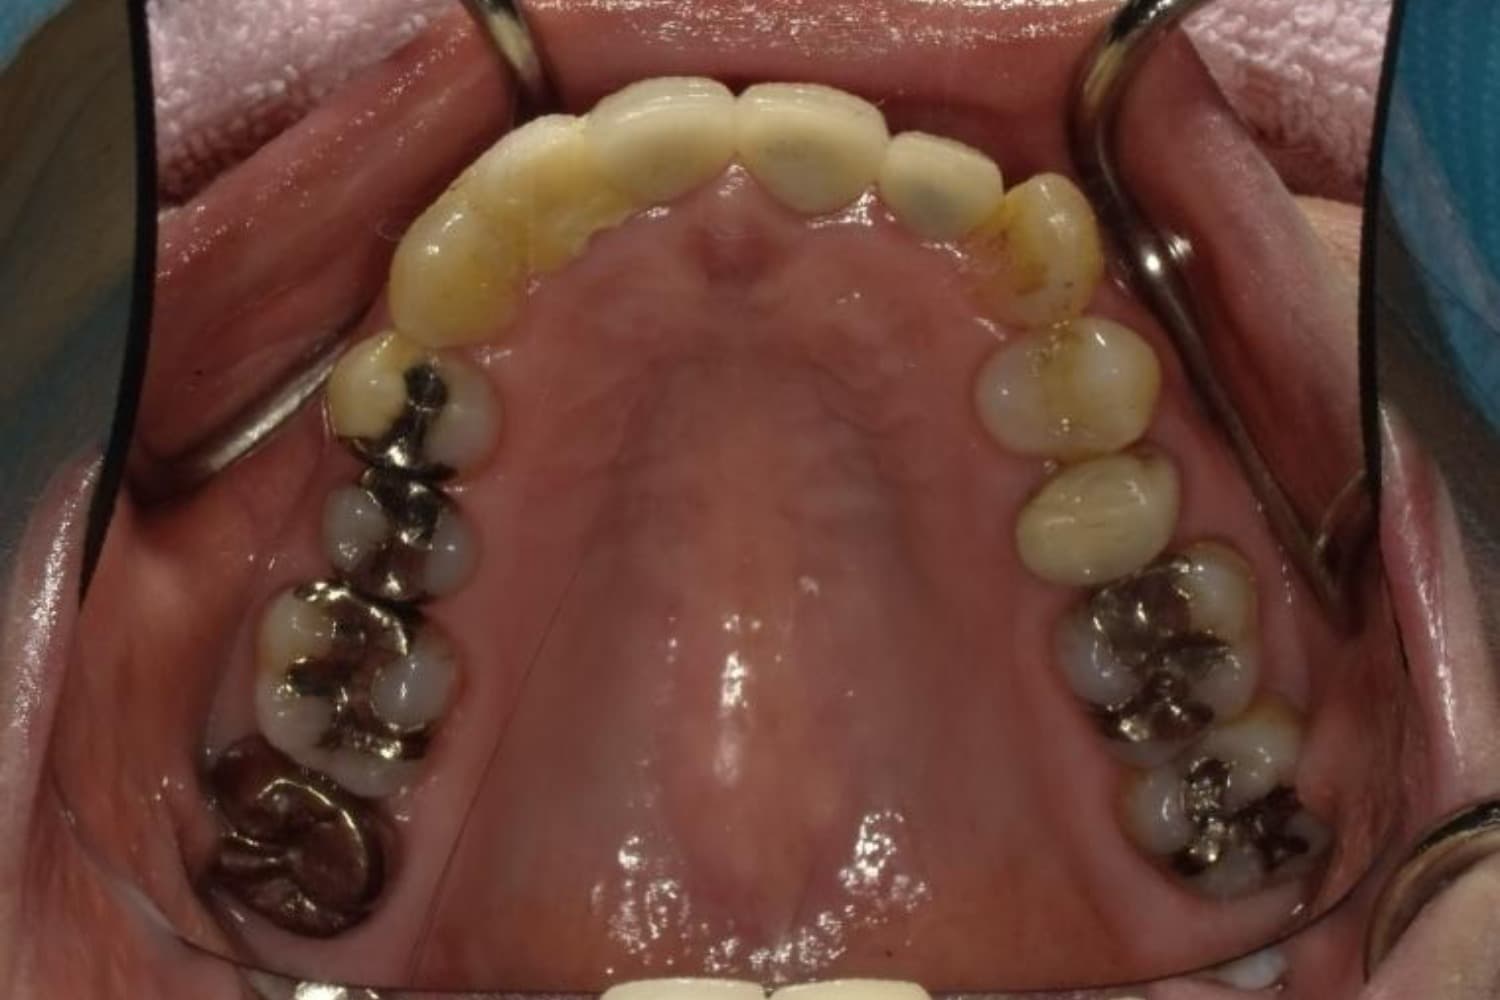

下顎大臼歯3本欠損症例

Before

After

左下第一大臼歯は保存が困難な状態であったため抜歯をおこないました。あわせて、ご来院時から欠損していた右下第一・第二大臼歯も含め、欠損部の補綴方法についてご説明し、インプラント治療を選択されました。

年齢

60歳

性別

男性

主訴

左下の第一大臼歯は別の医院で治療中でしたが、治療が思うように進まず、加えて他の箇所にも痛みが続いたことから、当院にご相談いただきました。

治療期間

10ヵ月

費用

140万円

副作用・リスク

インプラント治療は外科的な処置を伴い、多少の腫れや痛みが出ることがあります。 多くの場合は鎮痛薬で和らげることができます。